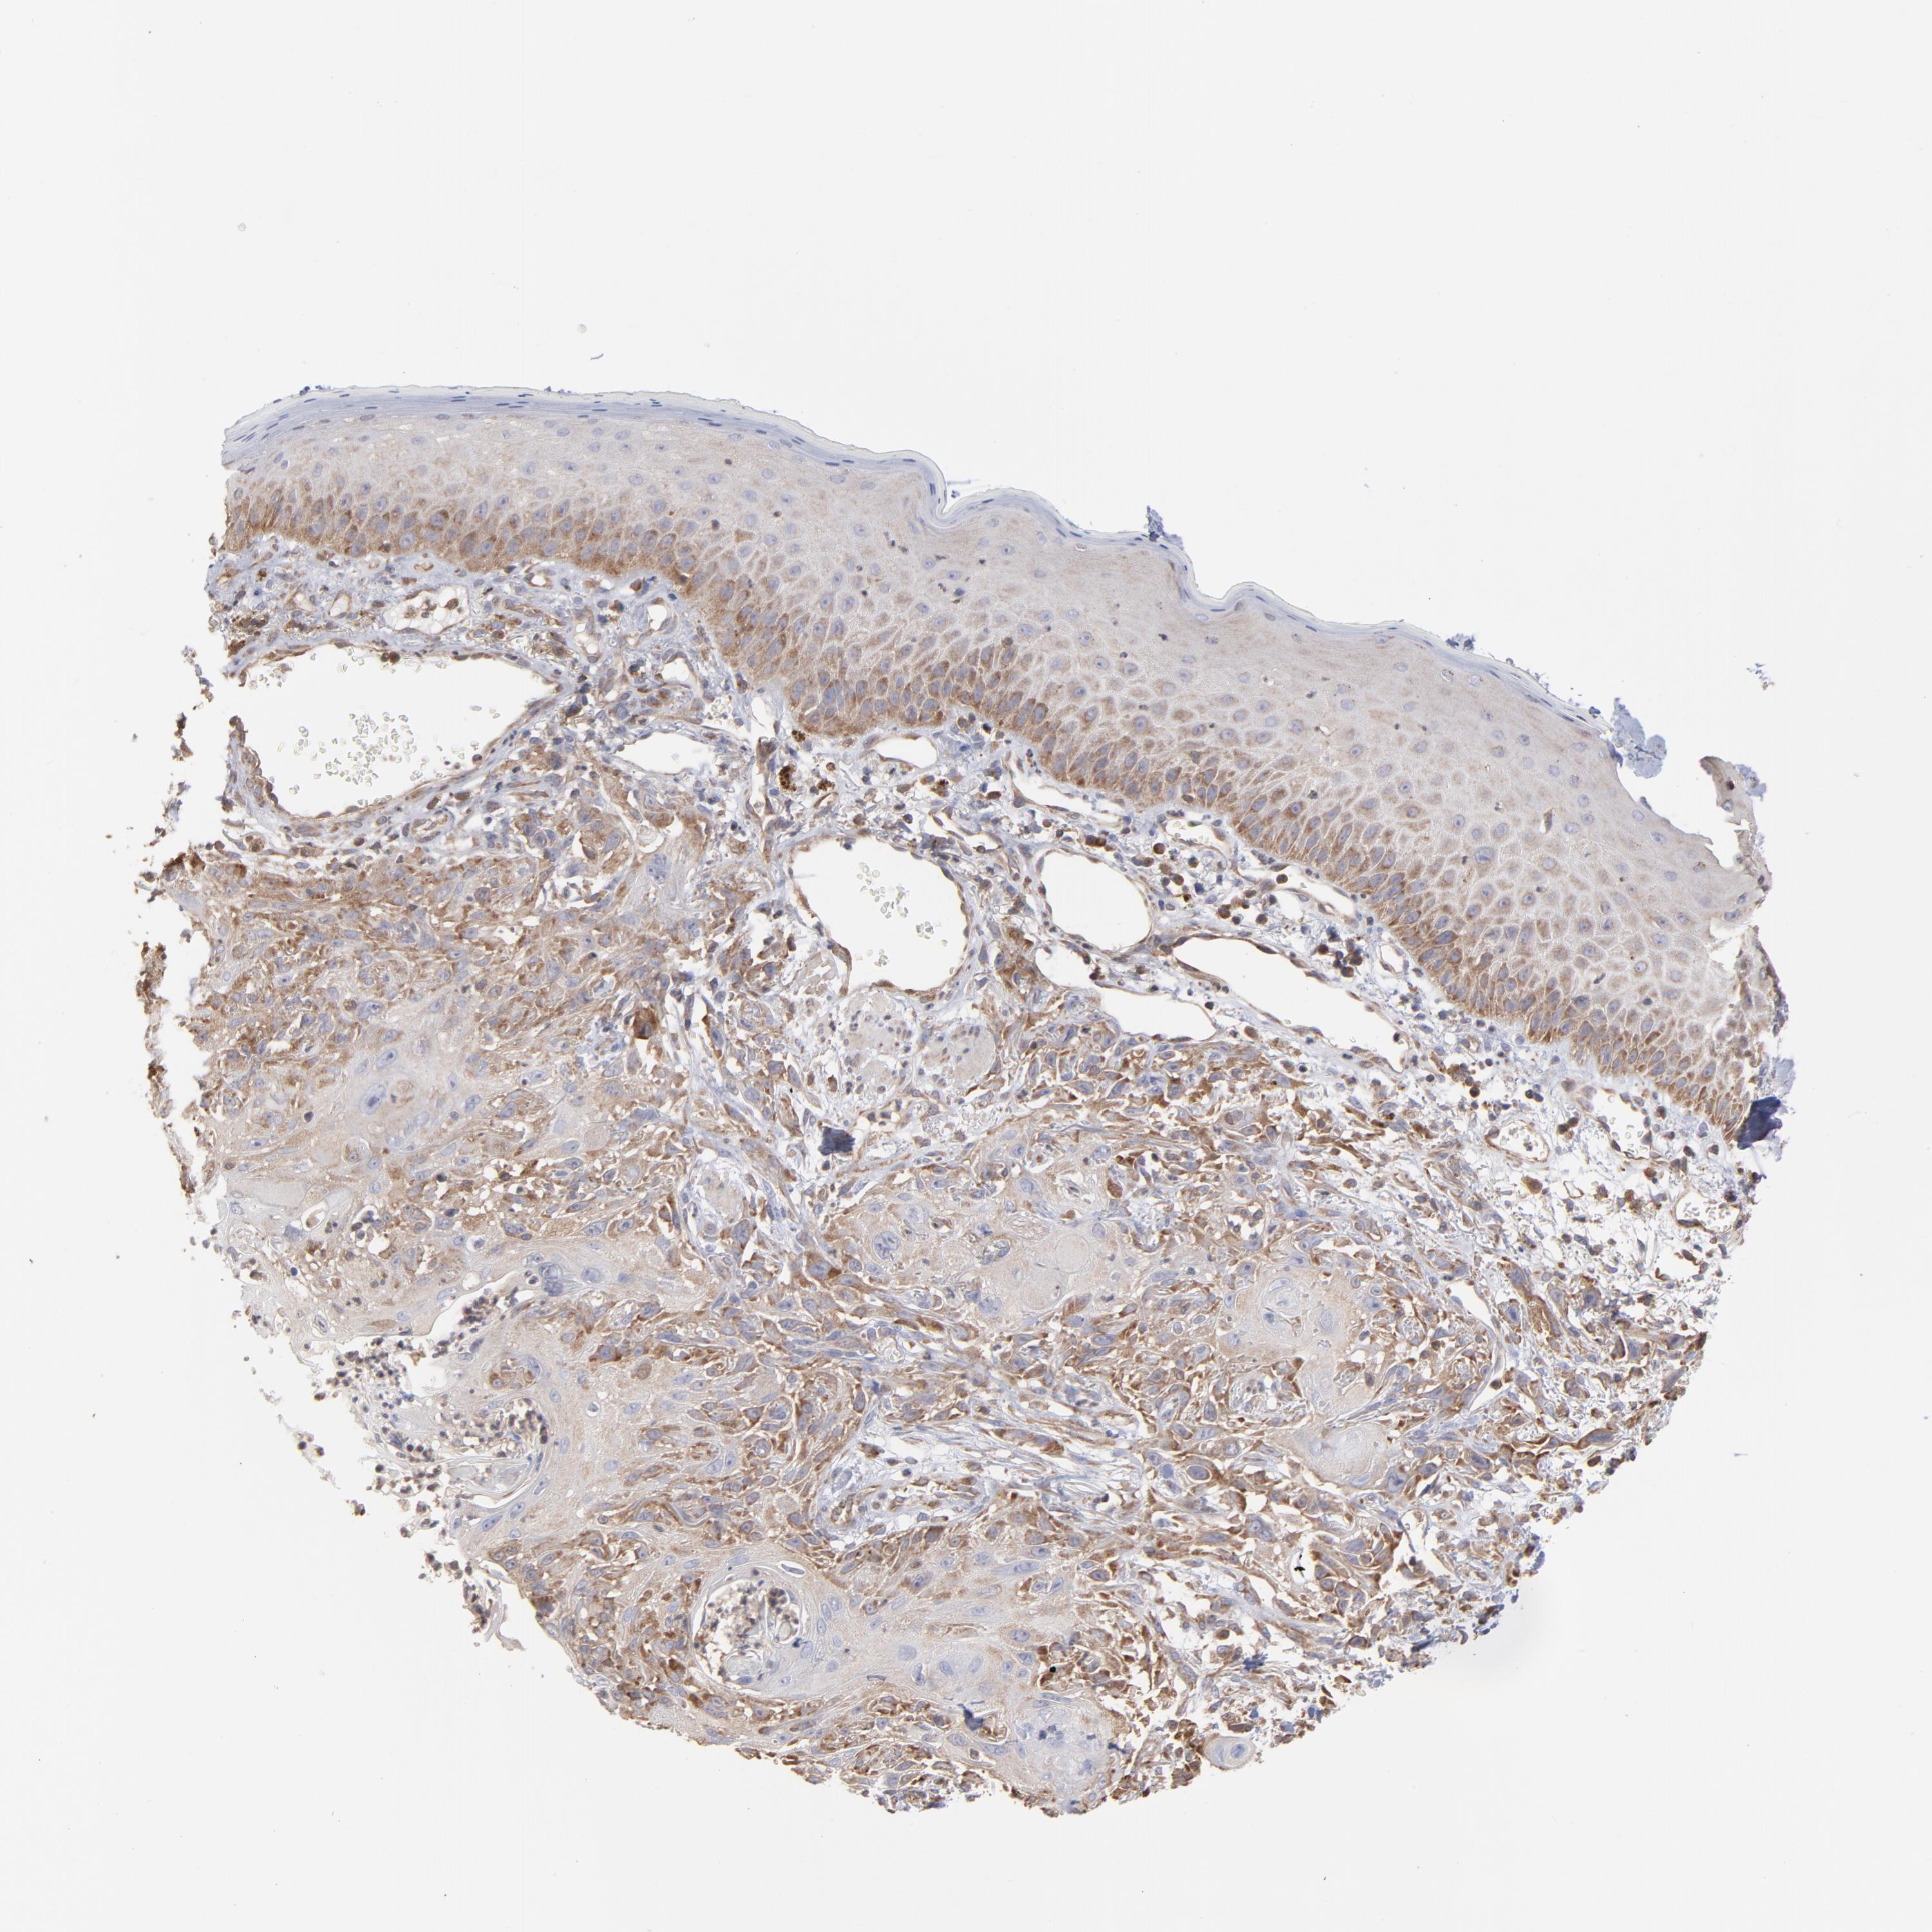

SKIN CANCER - Protein expressioni

A mouse-over function shows sample information and annotation data. Click on an image to view it in a full screen mode. Samples can be filtered based on level of antibody staining by selecting one or several of the following categories: high, medium, low and not detected. The assay and annotation is described here.

Antibody stainingi

Antibody staining in the annotated cell types in the current human tissue is reported as not detected, low, medium, or high, based on conventional immunohistochemistry profiling in selected tissues. This score is based on the combination of the staining intensity and fraction of stained cells.

Each image is clickable and will lead to virtual microscopy that enables deeper exploration of all samples and also displays staining intensity scores, fraction scores and subcellular localization as well as patient and tissue information for each sample.

Antibody HPA003600

Staining

High

Medium

Low

Not detected

Intensity

Strong

Moderate

Weak

Negative

Quantity

>75%

75%-25%

<25%

None

Location

Nuclear

Cytoplasmic/membranous

Cytoplasmic/membranous,nuclear

Squamous cell carcinoma, NOS